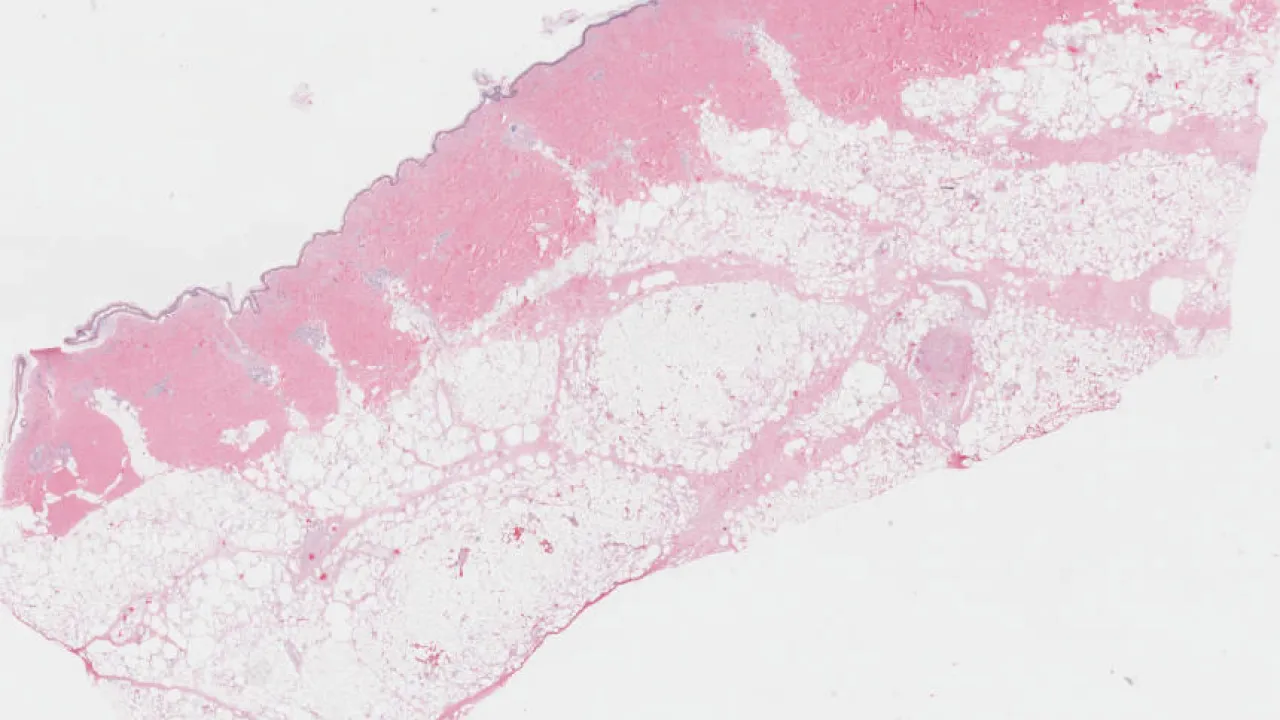

Skin, Subcutaneous Fat Necrosis